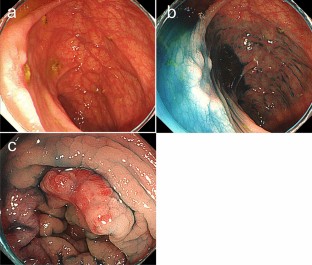

Gallbladder cancer is often diagnosed with metastasis and is known to have poor prognosis. Although, gallbladder cancer often metastasizes to liver, lung, or lymph nodes, metastasis to gastrointestinal tract is not common. Several autopsy studies reported colorectal metastasis from gallbladder cancer, but most of these cases were supposed to be gastrointestinal invasion from peritoneal dissemination. We experienced a rare case of hematogenous colon metastasis from gallbladder cancer. Colonoscopy for a 76-year-old man who was diagnosed as gallbladder cancer revealed two 5-mm flatly elevated lesions with central erosion in the transverse and sigmoid colon. Endoscopic mucosal resection (EMR) revealed poorly differentiated adenocarcinoma in hematoxylin and eosin staining. Additional immunohistochemistry examination showed strongly positive CK7 expression with negative CDX2, and suggested colon metastases from gallbladder cancer. Despite the positive vertical margin in EMR specimens, autopsy finding denied colorectal invasion from peritoneal dissemination and proved vascular spread colon metastases. Gastrointestinal metastasis is often misdiagnosed as a primary tumor, and thus, it is important to recognize gallbladder cancer as a potential origin of gastrointestinal metastasis.

Fig. 3